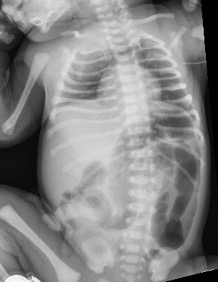

Two unrelated male neonates were born at term in the same hospital on the same day. Both mothers had prenatal care established in the first trimester, and both pregnancies were uncomplicated.